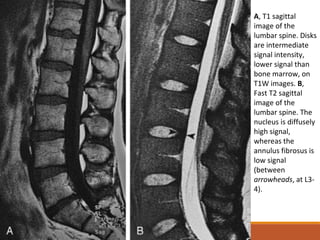

◦Na RM, o disco ideal normal possui sinal de baixa intensidade em

T1, tendo sinal discretamente mais baixo que a medula vermelha

adjacente normal e muito similar ao músculo.

◦As imagens em T2 mostram sinal difuso de intensidade alta em

todo o disco, exceto pelas fibras externas do anel, que possuem

sinal homogeneamente baixo.